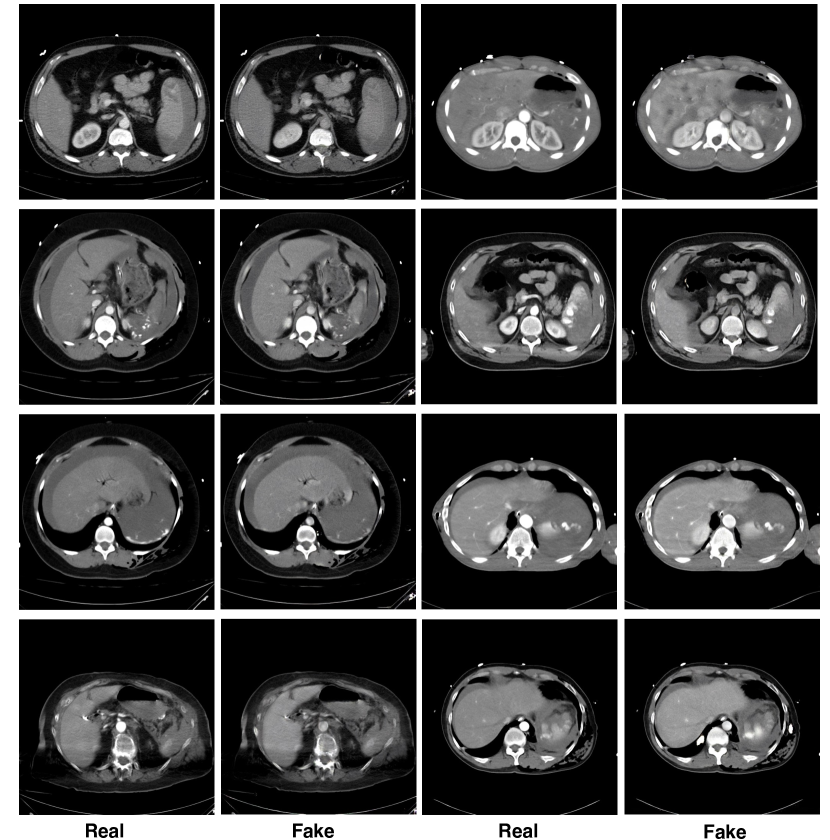

Refer to caption

Figure 3: Real images vs. synthetic images. Synthesized injury spots are inpainted onto the generated images.

Fig. 3 illustrates a few pairs of examples of the original image and the generated synthetic image. We can see that our phase translation model have successfully brought contrast and texture changes to the original images, which in turn make them appear more similar to images from the other phase. This means that the new texture of the splenic vascular injury can be inpainted onto the generated images. Therefore, unlike previous studies [42, 43], here the real and the synthetic data will be jointly trained using the subsequent segmentation network in a self-learning manner. Self-learning, or self-training, usually consists the following steps: 1) train a teacher model on labeled images and use it to propagate labels from the labeled to the unlabeled data; 2) then use the larger set combined of both labeled and pseudo labeled data for training a student model. Then this process can be iterated by putting back the student as the teacher. This approach has been successfully applied to multiple natural and medical imaging tasks [50, 51, 17, 19, 20]. In our method, similarly, we train the external attention assisted model in a similar manner where it propagates labels from the internal labeled images to the synthetic images, and then using the larger, newly labeled set for training. The detailed training algorithm is illustrated next.